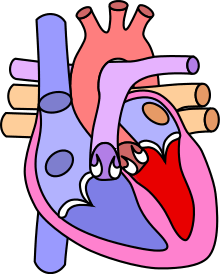

| Diagram of a healthy heart and one with tetralogy of Fallot | |

The cause is typically not known. Risk factors include a mother who uses alcohol, has diabetes, is over the age of 40, or gets rubella during pregnancy. It may also be associated with Down syndrome.[4] Classically there are four defects:[2]

- a ventricular septal defect, a hole between the two ventricles

- pulmonary stenosis, narrowing of the exit from the right ventricle

- right ventricular hypertrophy, enlargement of the right ventricle

- an overriding aorta, which allows blood from both ventricles to enter the aorta

As such, by definition, tetralogy of Fallot involves four heart malformations which present together:

| Pulmonary Infundibular Stenosis | A narrowing of the right ventricular outflow tract. It can occur at the pulmonary valve (valvular stenosis) or just below the pulmonary valve (infundibular stenosis). Infundibular pulmonic stenosis is mostly caused by overgrowth of the heart muscle wall (hypertrophy of the septoparietal trabeculae),[15] however the events leading to the formation of the overriding aorta are also believed to be a cause. The pulmonic stenosis is the major cause of the malformations, with the other associated malformations acting as compensatory mechanisms to the pulmonic stenosis.[16] The degree of stenosis varies between individuals with TOF, and is the primary determinant of symptoms and severity. This malformation is infrequently described as sub-pulmonary stenosis or subpulmonary obstruction.[17] |

| Overriding aorta | An aortic valve with biventricular connection, that is, it is situated above the ventricular septal defect and connected to both the right and the left ventricle. The degree to which the aorta is attached to the right ventricle is referred to as its degree of "override." The aortic root can be displaced toward the front (anteriorly) or directly above the septal defect, but it is always abnormally located to the right of the root of the pulmonary artery. The degree of override is extremely variable, with 5-95% of the valve being connected to the right ventricle.[15] |

| Ventricular septal defect (VSD) | A hole between the two bottom chambers (ventricles) of the heart. The defect is centered around the most superior aspect of the ventricular septum (the outlet septum), and in the majority of cases is single and large. In some cases thickening of the septum (septal hypertrophy) can narrow the margins of the defect.[15] |

| Right ventricular hypertrophy | The right ventricle is more muscular than normal, causing a characteristic boot-shaped (coeur-en-sabot) appearance as seen by chest X-ray. Due to the misarrangement of the external ventricular septum, the right ventricular wall increases in size to deal with the increased obstruction to the right outflow tract. This feature is now generally agreed to be a secondary anomaly, as the level of hypertrophy tends to increase with age.[18] |